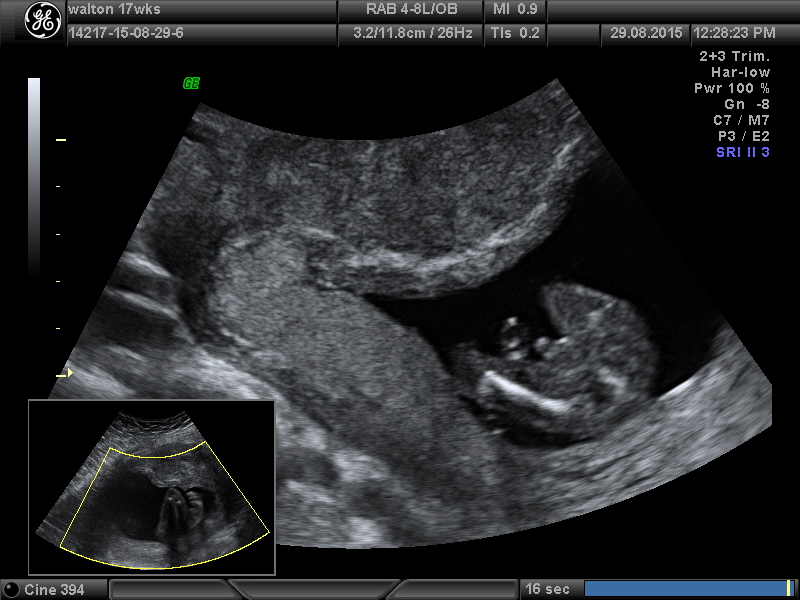

So is this a excellent boy shot or questionable ??

Definitely 100% boy! That's a definite turtle shot!